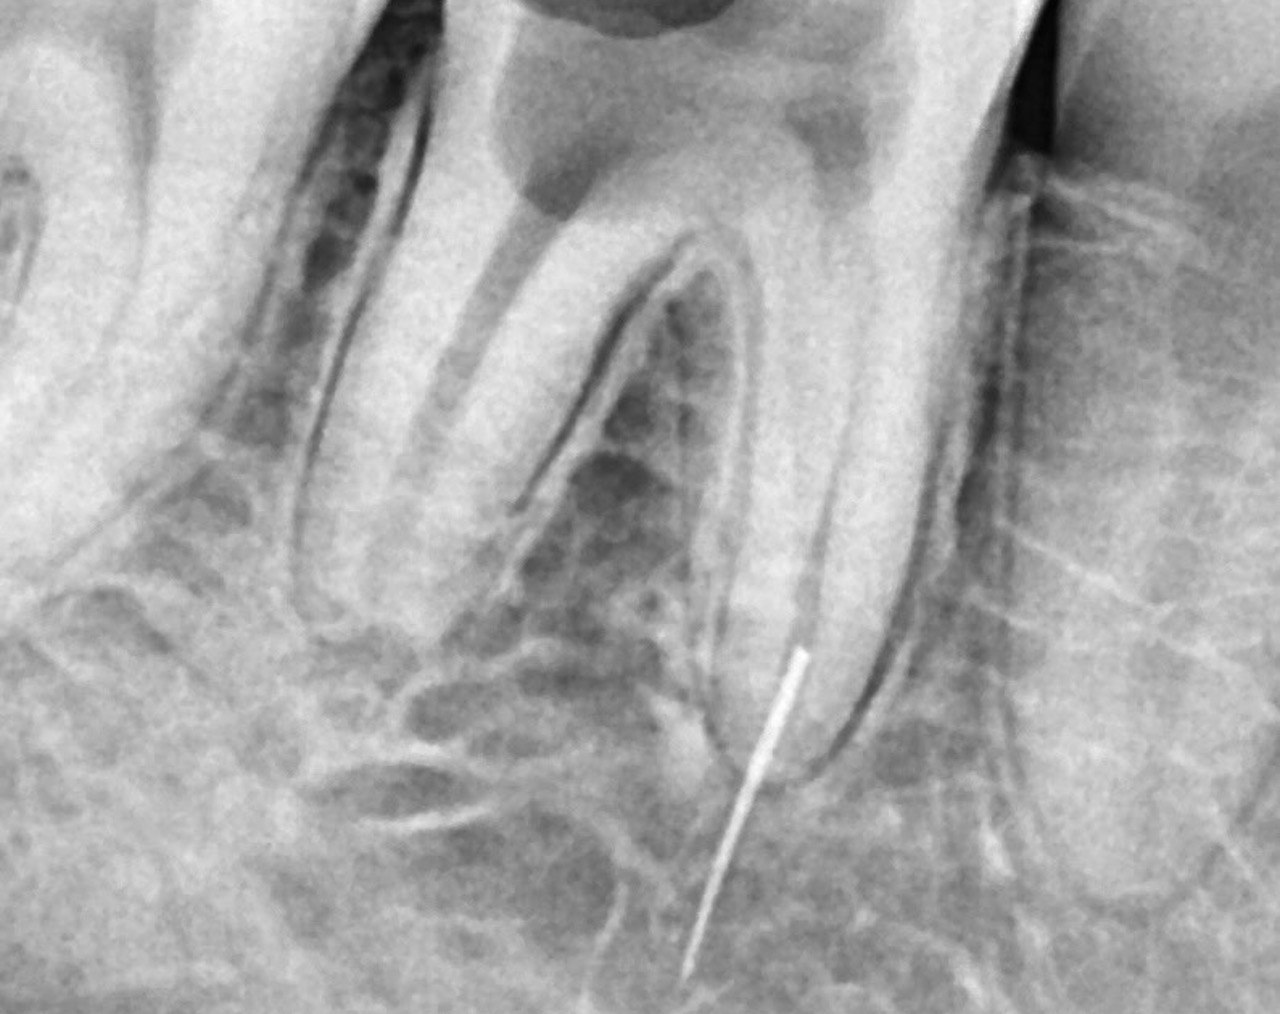

3. What Condition can be seen in this X ray regarding the tooth # 2.2?